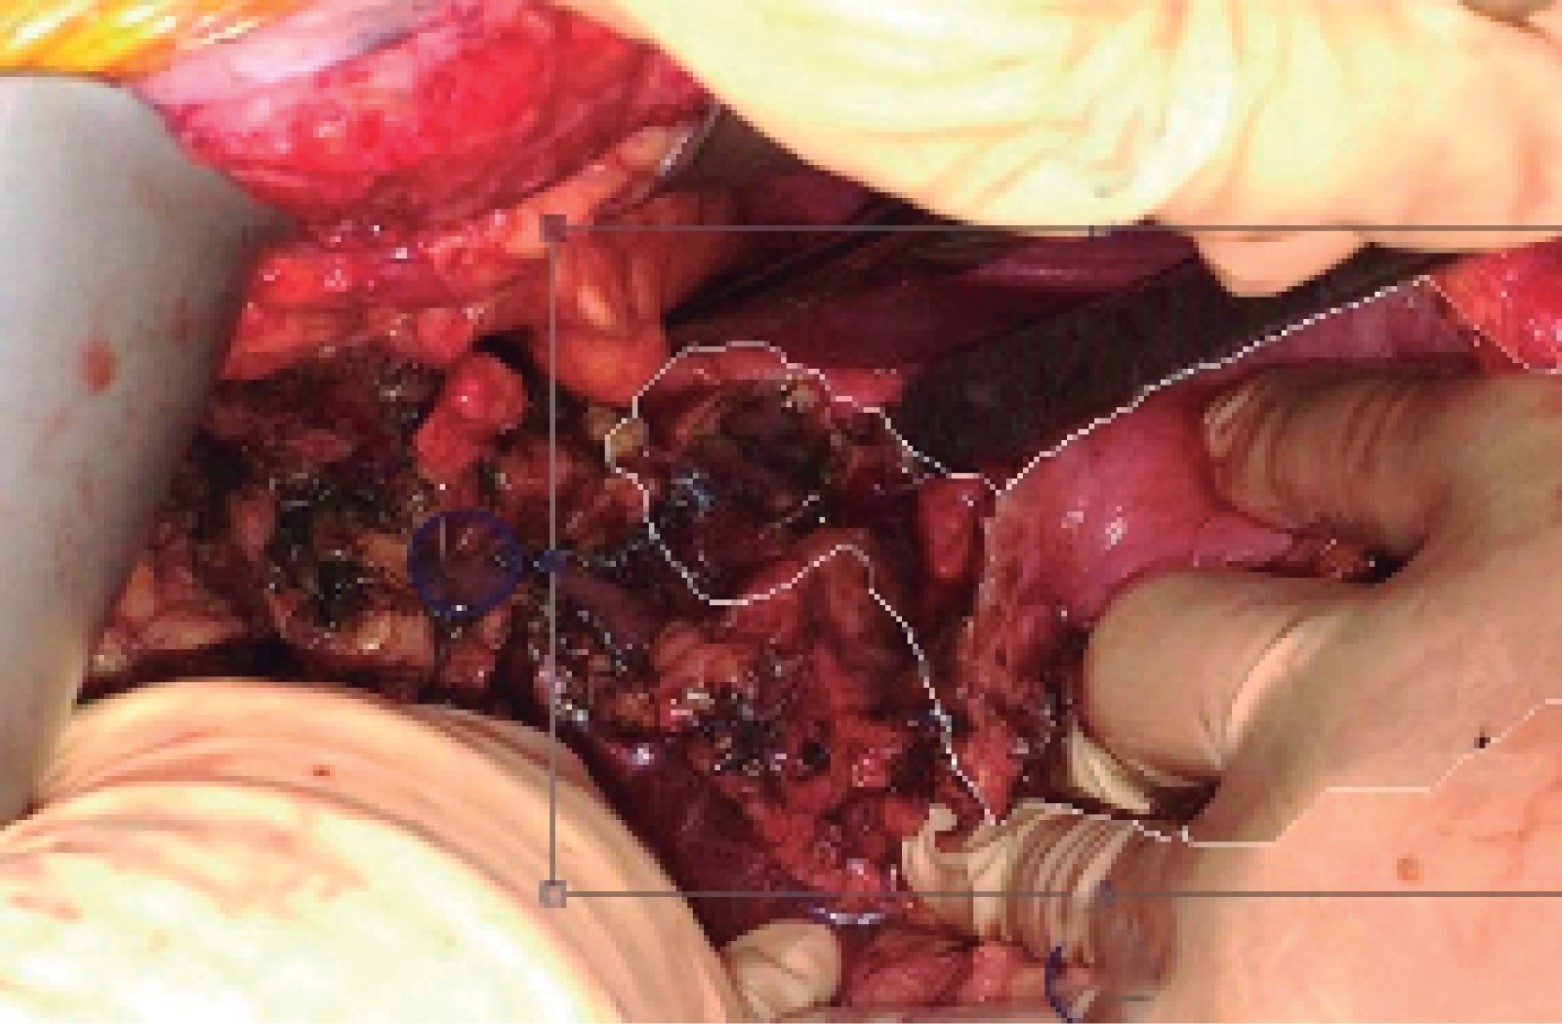

An emergency exploratory laparotomy was performed, which revealed the presence of a circumferential duodenal ulcer with a complete section of the first portion of the duodenum (Figure 2), abundant free bile fluid, and coffee wells; duodenal stump closure was performed with duodenostomy, antrectomy and manual Braun's omega gastrojejunal bypass with the placement of closed drains adjacent to the anastomosis, with a procedure duration of four hours.

Figure 2